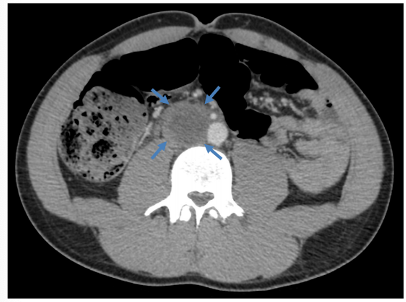

What kidn of imaging is this and what is shown?

What kind of imaging is this and what is shown?